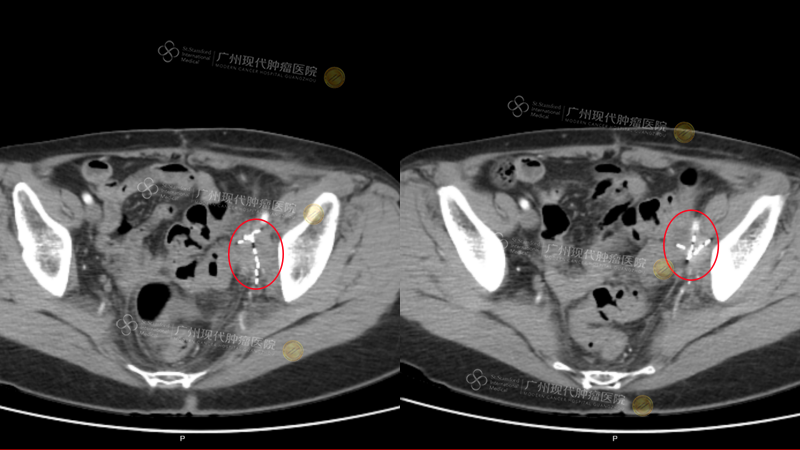

(Pelvis: Tumor reduced by 80% after two treatments) (The white highlights indicate the implanted particles)

(Re-examination on December 19, 2025, after four treatments, revealed that the tumor was essentially completely deactivated)